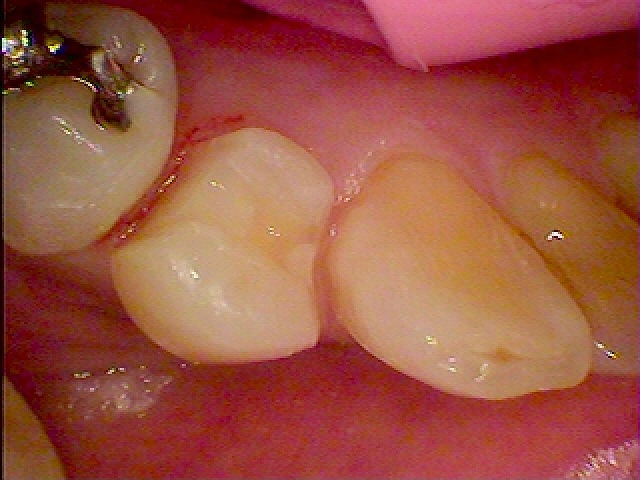

右下の4番部になります

虫歯が存在していました

除去して白い樹脂にて修復、覆罩を行っています

CR樹脂にて覆罩を行っています

セレックセラミックを用いた審美治療になります

本来の歯のようにきれいに仕上がりました